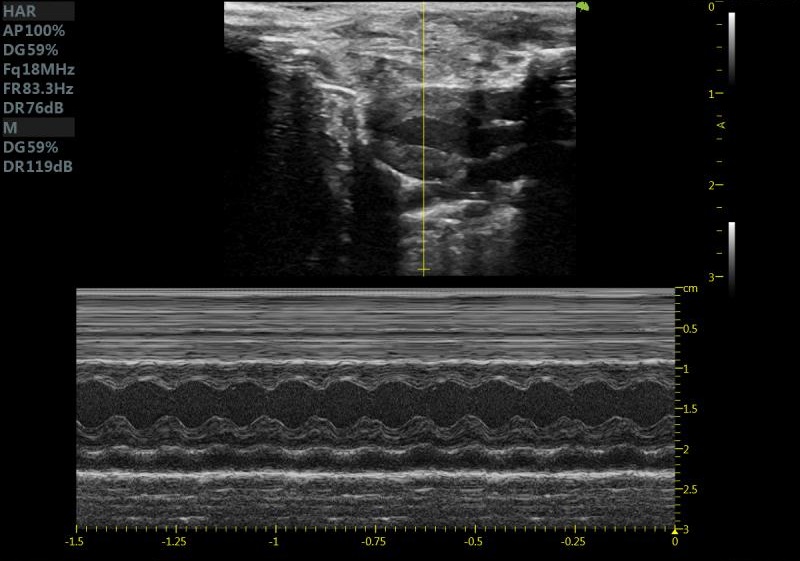

小鼠长轴M型 小鼠短轴M型

大鼠短轴M型 大鼠长轴M型